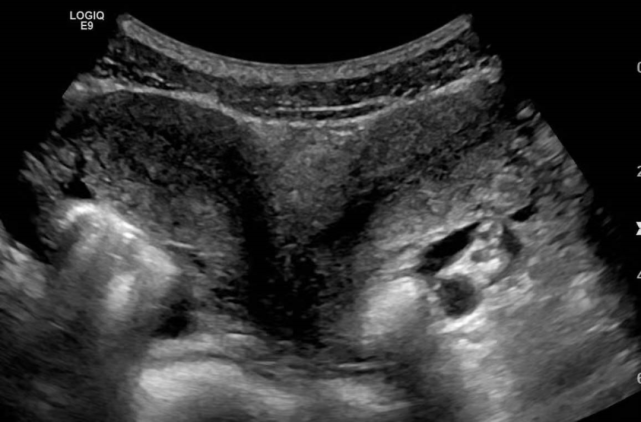

双子宫并不难诊断,一般情况下B超检查就可以看出来。B超不仅相对来说花费比较低廉,而且操作也比较简单。

图片

先天性的子宫畸形也分为很多种,除了双子宫,常见的还有纵隔子宫与双角子宫,在进行超声检查的时候,除了要评估宫底的外部轮廓,还需要评估肾脏有无相关异常。

对于双子宫来说,在B超影像下,可以查见2个相隔较远的子宫角,伴有较深的宫底凹陷,而且医生可以通过窥器检查,发现2个宫颈。不过要是困难病例,那么可能还需要MRI来更好显示复杂畸形;

阴道B超相对来说探查更清晰一些,对于不能耐受或拒绝阴道探头三维超声诊断的年轻女性,可以考虑使用MRI。